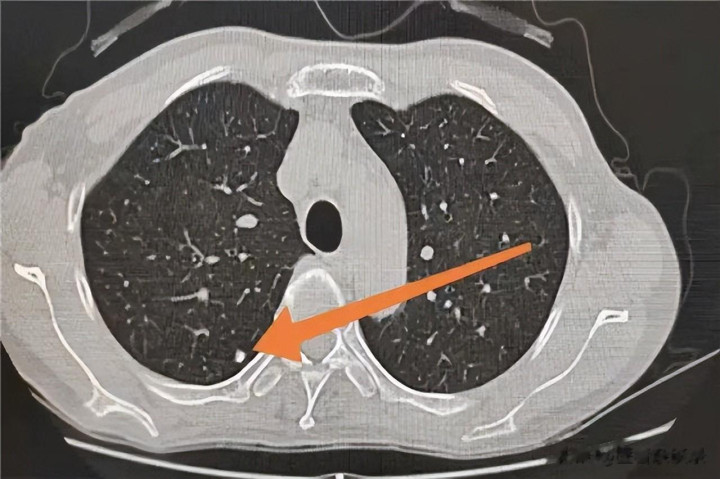

天然,咱们也不可完全排斥那不到 10% 的恶性可能,大夫在判断结节性质时,主要看三个缺欠商量,大小、密度和格式。频频而言,结节大小与良性概率存在一定关系,一般情况下,结节尺寸越小,其为良性的可能性越大,此类结节频频在医学不雅察中,因其风险低微而无需过度担忧。

而在密度方面,纯磨玻璃结节诚然听起来吓东说念主,但它们频频助长极其巩固,被称为“懒癌”,即便真实是早期肿瘤,也有很长的窗口期去不雅察和处理。最需要警惕的是搀和磨玻璃结节,也即是中间有实心因素,周围一圈隐约的结节,这类结节的恶性风险相对较高,需要密切随访。

结节的格式颇为缺欠,良性结节一般旯旮平滑、轮清亮翠,与之不同,恶性结节常呈“青脸獠牙”之态,旯旮伴有毛刺、分叶。或者把周围的血管和胸膜拉扯变形,大夫恰是通过这些细节,逢迎患者的年纪、抽烟史、家眷史等抽象因素,来评估风险。